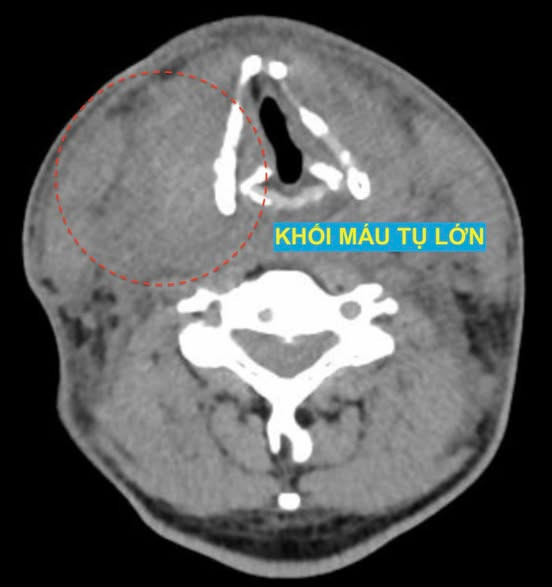

Bệnh viện Đại học Y vừa tiếp nhận một bệnh nhân chảy máu nghiêm trọng sau chọc tế bào tuyến giáp. Một bệnh nhân sau khi chọc tế bào tuyến giáp buổi sáng, đến trưa xuất hiện căng tức vùng cổ, mệt mỏi, nhợt nhạt. Khi vào khoa Cấp cứu, chụp chiếu phát hiện khối máu tụ lớn vùng cổ kèm ổ chảy máu hoạt động ở thùy phải tuyến giáp.